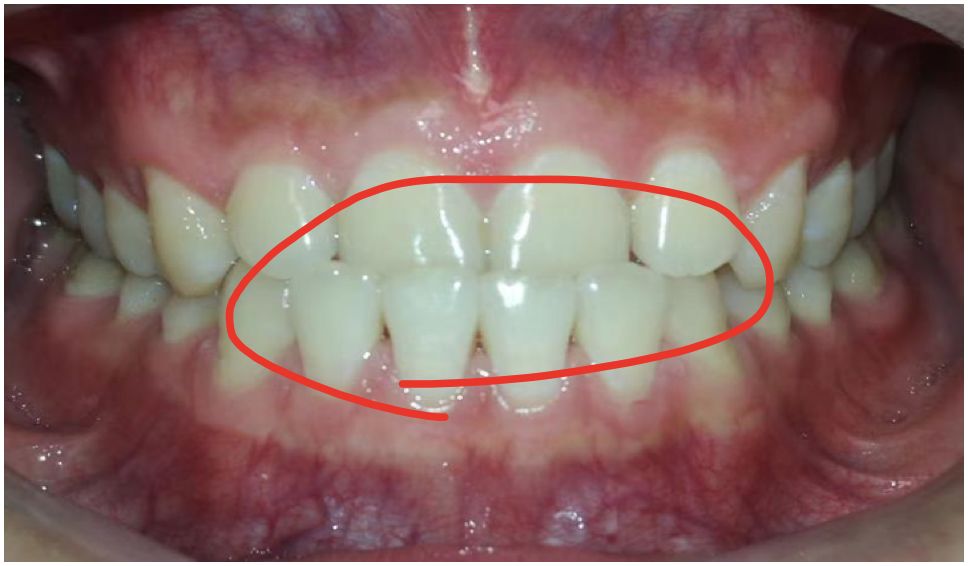

这个男生有前牙反颌问题,上门牙有明显的内凹。

这也是大家常说的“地包天”,会导致上唇后缩,下巴前突,笑起来更突出。

经检查,男生除了前牙反颌外,其他并无明显问题,本身磨牙咬合关系良好。